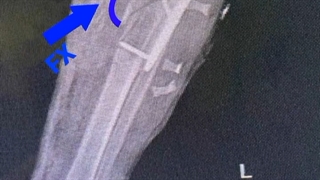

فیلم واقعی شکستگی سوپراکوندیلار هومروس

شکستگی سوپراکوندیلار هومروس